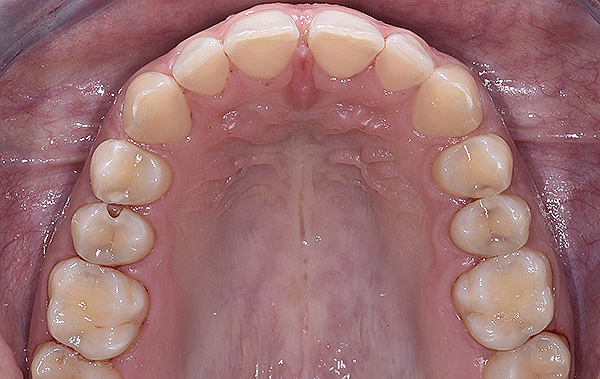

PREMESSA: in seguito all’estrazione dell’incisivo laterale superiore di destra, resasi necessaria per cause batteriche, si decide di affrontare il caso con il posizionamento di un impianto in sostituzione dell’elemento mancante dopo guarigione del sito infetto. Con tecniche rigenerative sia dei tessuti ossei mancanti a causa dell’infezione pregressa, sia dei tessuti gengivali che appaiono inizialmente troppo spostati in alto, si ripristina una corretta morfologia delle parabole (contorni) gengivali e delle papille interdentali (triangoli di gengiva tra due denti vicini).

Vengono utilizzati 2 tipi di provvisori: il primo, cementato ai denti vicini, viene utilizzato dal momento dell’estrazione del dente fino ad impianto osteointegrato (circa 6 mesi); il secondo, avvitato direttamente all’impianto, ha una funzione di prova estetica ma soprattutto di guida per la maturazione dei tessuti gengivali peri-implantari portandoli verso la maturazione completa prima di posizionare la corona finale in disilicato di litio.